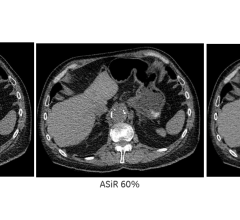

SPONSORED CONTENT — Fujifilm’s latest CT technology brings exceptional image quality to a compact and user- and patient ...